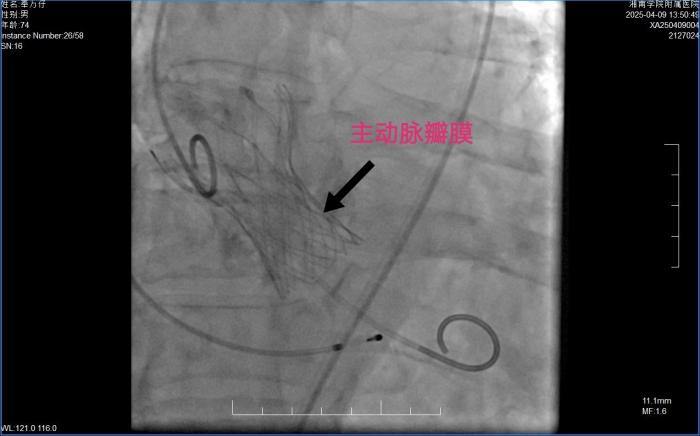

本网讯(通讯员 李虎)4月9日,湘南学院附属医院上演了一场生命接力。在多学科专家的紧密配合下,医院顺利为一名主动脉瓣膜重度狭窄的老年患者完成 “经导管主动脉瓣膜置换术(TAVR)”,这一成功案例标志着该院心血管内科专业再次实现重大突破,其心血管疾病诊疗能力和多学科协作水平迈上了新台阶。

为确保手术顺利进行,湘南学院附属医院迅速组建 TAVR 团队。心外科、麻醉科、神经内科、医学影像科以及超声科等多学科专家迅速行动,发挥各自专业优势,共同制定了详细周全的手术方案。手术过程中,医生们通过股动脉将人工主动脉瓣膜精准输送至主动脉瓣区并成功打开,顺利完成人工主动脉瓣膜置入,恢复了瓣膜的正常功能。手术十分成功,效果显著,得到了患者和家属的高度称赞。目前,奉老已康复出院。